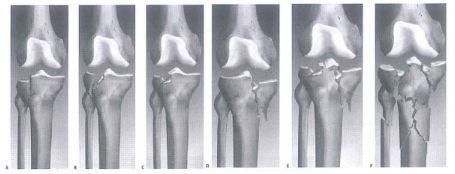

Nhiều bảng phân loại gãy mâm chày dựa vào hình thái tổn thương đã được để xuất, tuy nhiên, phân loại theo Schatzker được sử dụng rộng rãi ở Bắc Mỹ cũng như tại nước ta.

- Loại I: gãy mâm chày ngoài, gãy rời

- Loại li: gãy rời mâm chày ngoài kèm theo lún

- Loại III: gãy lún mâm chày ngoài

- Loại IV: gãy mâm chày trong

- Loại V: gãy 2 mâm chày

- Loại VI: gãy mâm chày thành nhiều mảnh kèm theo gãy thân xương chày

Hình 11.6. Phân loại theo Schatzker (Kenneth A. Egol, 2006)